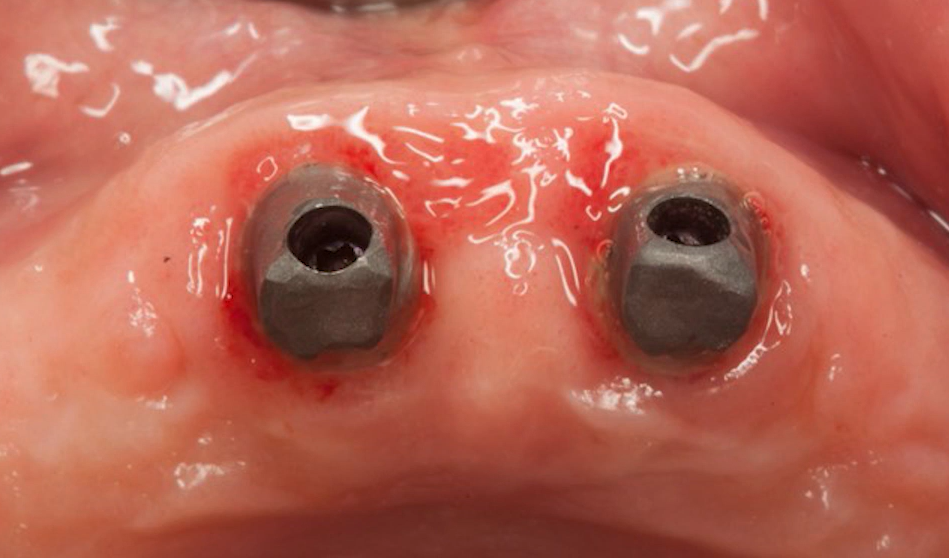

“Influence of Thin Mucosal Tissues on Crestal Bone Stability Around Implants With Platform Switching: A 1-year Pilot Study” (Dr. Linkevicius et al., 2010), published in Journal of Oral and Maxillofacial Surgery

This in vivo study from the same group shows a link between initial gingival level and the platform switching concept.

Volunteers had two identical implants placed side by side and, if possible, at the same level relative to the bone. The only difference was that one had a platform switch, while the other did not (see photo below).

Implant placement without platform switching (left) and with platform switching (right) – the goal is to determine the difference in marginal bone loss. YouTube/ Implantarium/ Rauf Aliyev

The initial gingival height was measured during the soft tissue dissection stage. The difference is visible in the image below. The top slide shows very thin gingiva, while the bottom slide shows much thicker gingiva.

The group with thin gingiva included patients whose soft tissue thickness was 2 mm or less, and the group with thick gingiva included patients whose thickness was more than 2 mm.

Measurements of the thickness of the gingiva above the alveolar ridge: upper image – thickness <2 mm; lower image – thickness >3 mm (almost 5 mm). YouTube/ Implantarium/ Rauf Aliyev

The results confirmed the research team’s hypothesis that the effectiveness of platform switching is directly related to the thickness of the original gingiva.

Here’s an X-ray of one of the patients in the thin gingiva group. The left image shows the bone level at the time of implant placement, and it’s clear that both implants are positioned at bone level. The right image was taken 12 months later, and it shows that bone remodeling has occurred, and the necks of both implants were exposed. Moreover, the level of bone loss was almost the same for both platform-switching and non-platform-switched implants. Whereas in the group of patients with gingival thickness greater than 2 mm, bone loss around implants with platform switching was noticeably less.

X-rays of the same patient: bone level around implants at the time of placement (left) and after 12 months (right), the right image shows noticeable and almost equal bone loss around both implants. YouTube/ Implantarium/ Rauf Aliyev